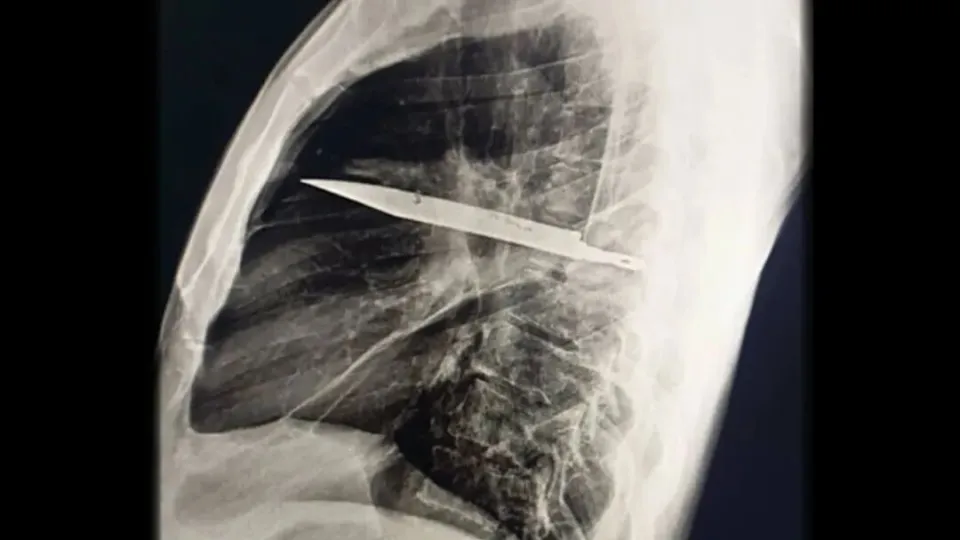

Khi thăm khám, bác sĩ nhận thấy ngực phải của bệnh nhân không nở ra đầy đủ khi hít vào, kèm theo lỗ rò rỉ dịch mủ có mùi hôi. Kết quả chụp X-quang khiến toàn bộ ê-kíp choáng váng: một lưỡi dao lớn gãy nằm gọn trong khoang ngực , kéo dài từ vùng xương bả vai phải đến trước xương sườn.

Phim chụp X-quang ngực của bệnh nhân cho thấy một lưỡi dao lớn găm vào giữa lồng ngực